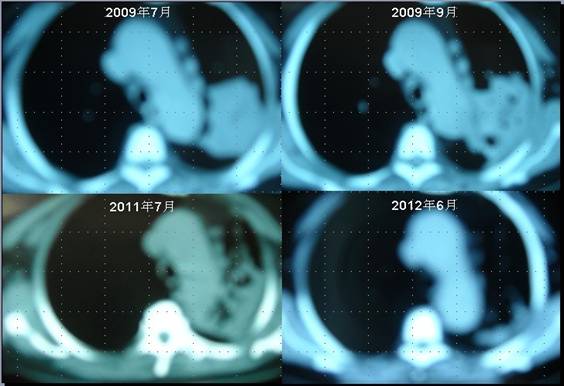

患者李某某,女,64歲,于2009年6月因咳嗽、喘憋、痰中帶血,經(jīng)CT及病理等相關(guān)檢查確診為右肺上葉粘液腺癌,縱膈淋巴結(jié)轉(zhuǎn)移, 左胸膜轉(zhuǎn)移,胸腔積液,因病情及體質(zhì)的原因無法接受手術(shù)及放化療等殺傷性治療,采用“中醫(yī)調(diào)胃、強腎、止血、化巖法”先后共治療8個月,現(xiàn)患者已有質(zhì)量的存活近3年。目前隨訪患者飲食、睡眠、體力均好,可獨立完成日常家務(wù),如今患者已經(jīng)67歲。

肺癌病人李XX采用“董氏治癌法”治療前后CT變化